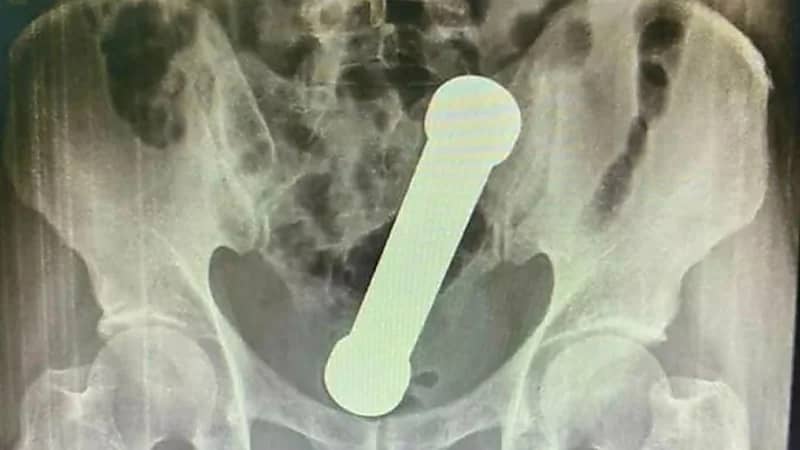

كشفت مستشفى ماناوس بالبرازيل عن إنقاذ حياة مُسن برازيلي دخل في جسده دمبل بوزن 2 كيلوجرام في حادثة غريبة لم تشهدها من قبل .

وبعد أن اجري المسعفين تصوير باطنه بالأشعة السينية للرجل الذي يبلغ من العمر54 عاماً قرروا ضرورة إزالة الدمبل بأيديهم.

ولجأوا لاستخراج الجسم الغريب يدويًا بطريقة وحشية ومُخيفة، وذلك بعدما فشلوا في استخراجه باستخدام الملقط.

وأوضح تقرير الفريق الجراحي ، إلى أن الأجسام الشرجية المحتجزة تمثل شكوى نادرة في غرفة الطوارئ و تؤثر بشكل أساسي على الذكور الذين تتراوح أعمارهم بين 20 و 40 عاماً.